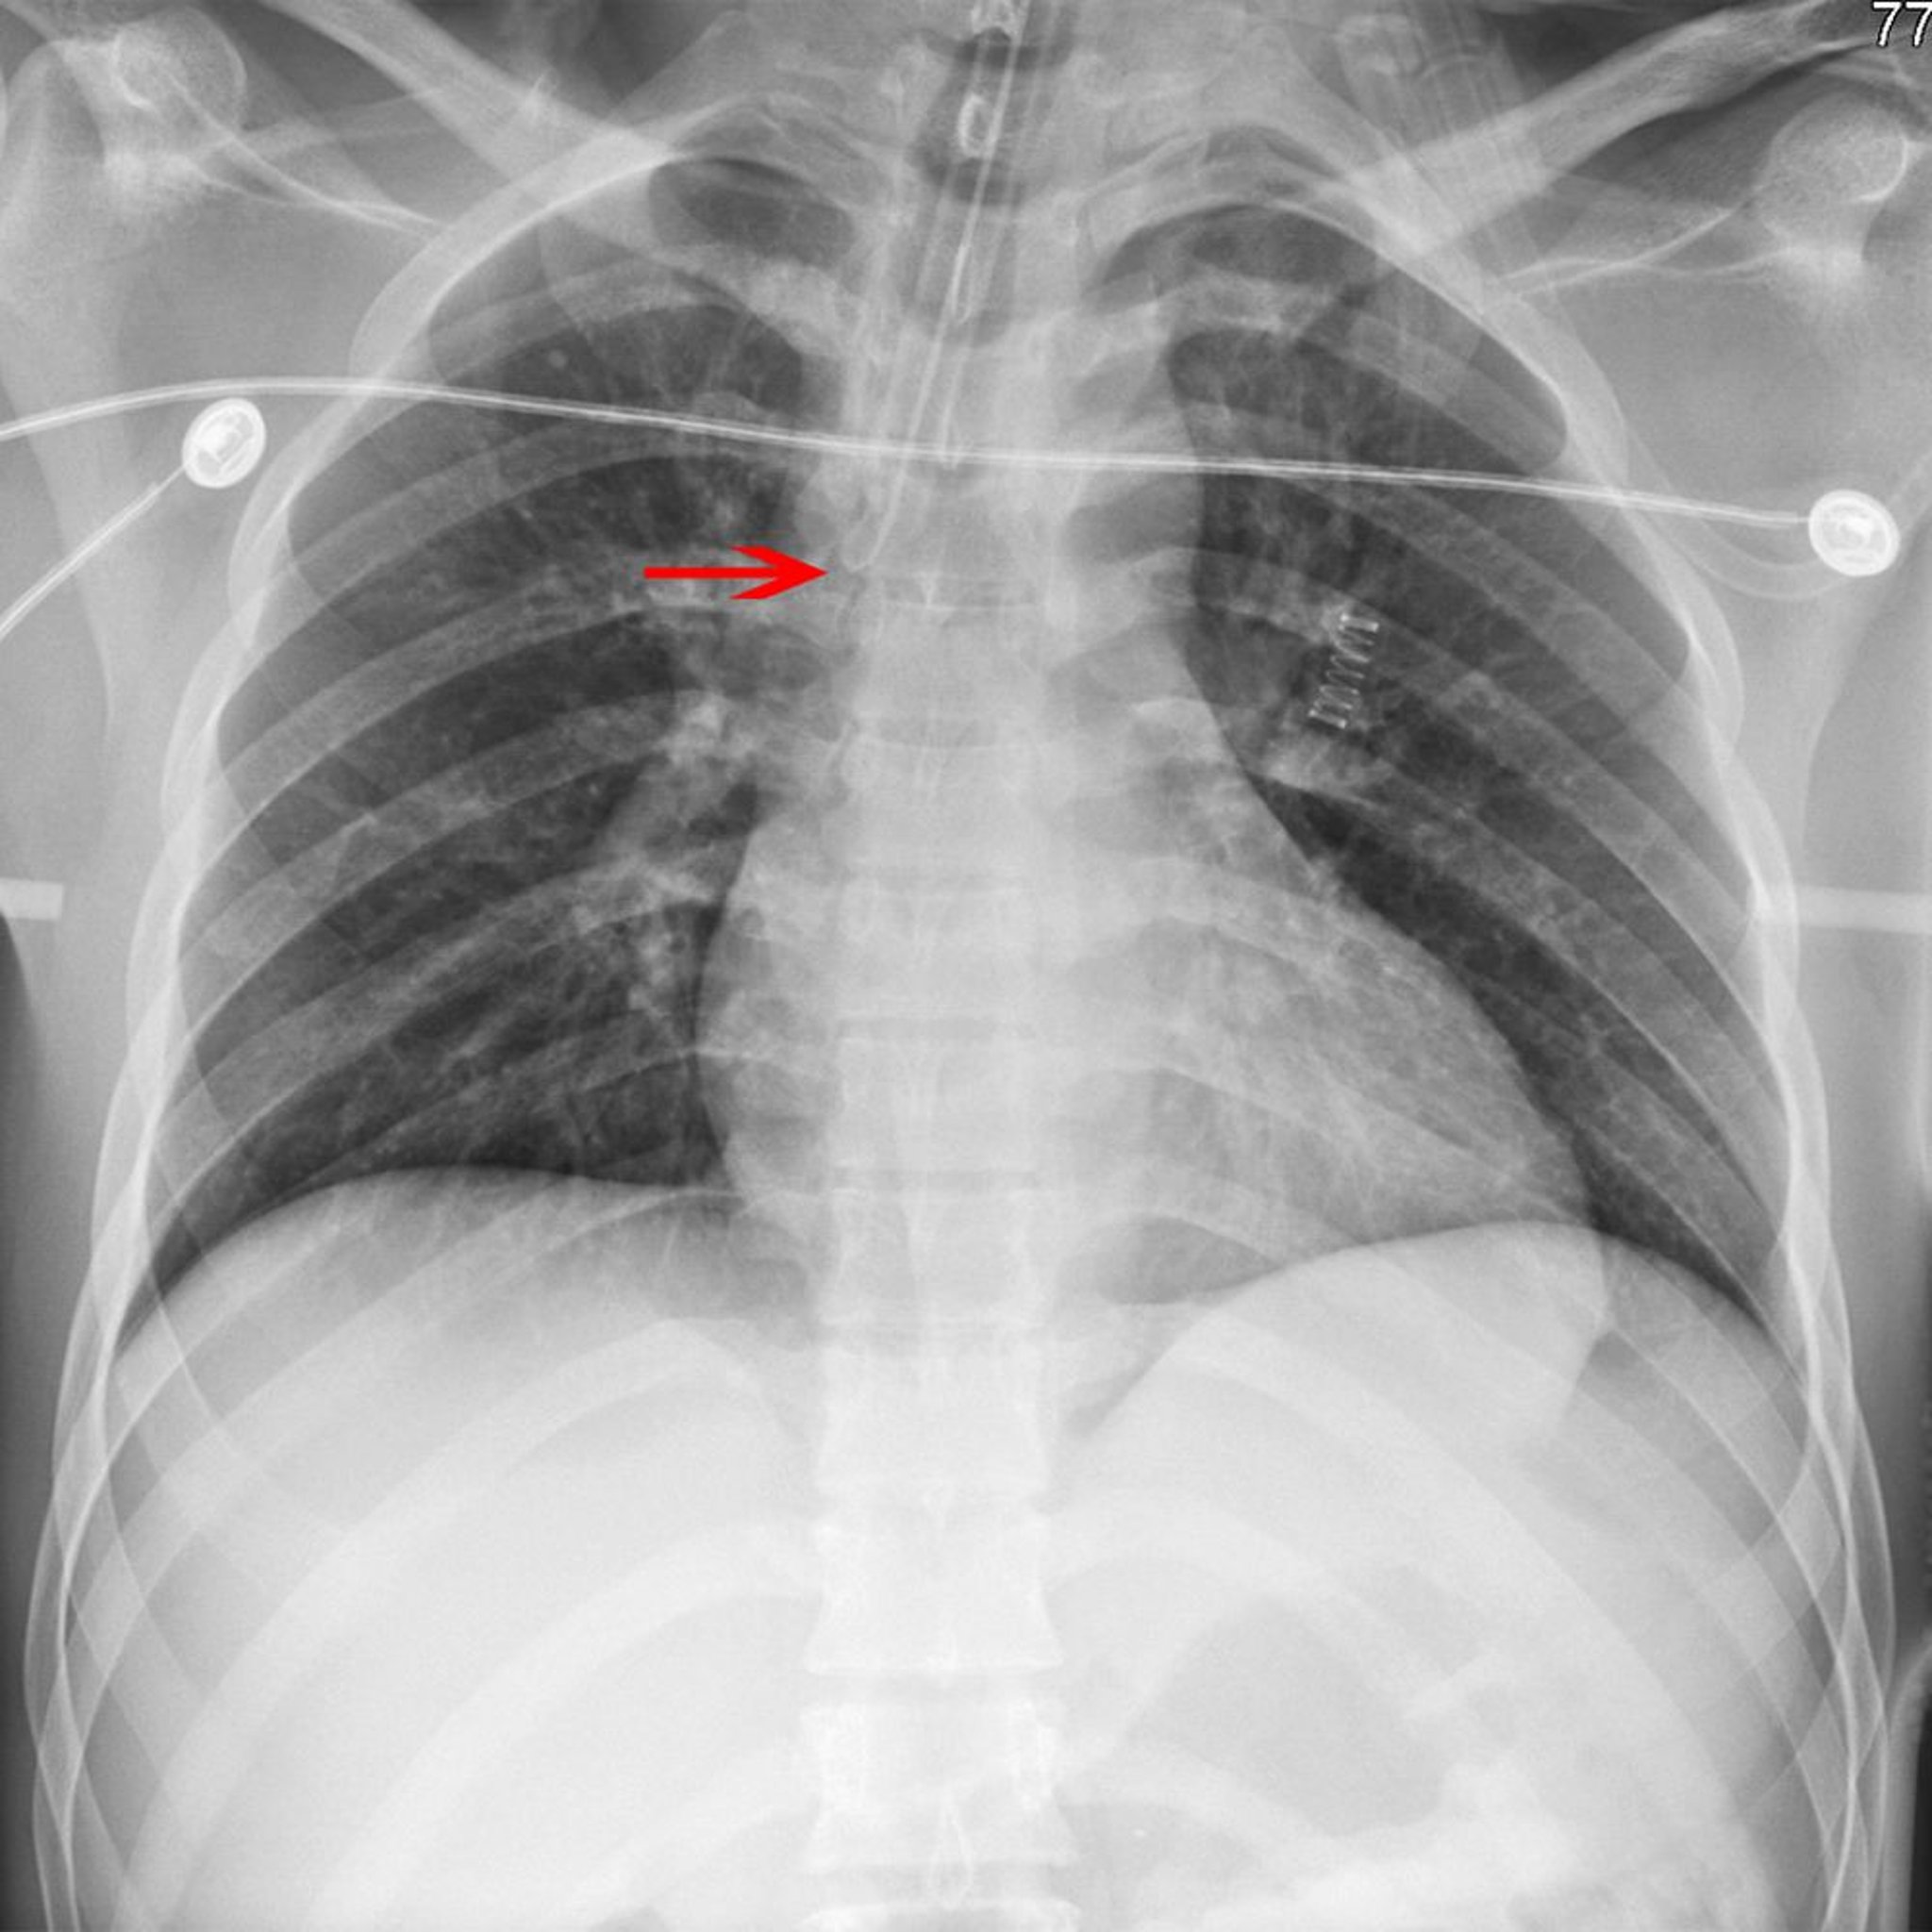

X线显示错误放置的气管内插管

箭头指向未正确放置在右主支气管的气管导管尖端。